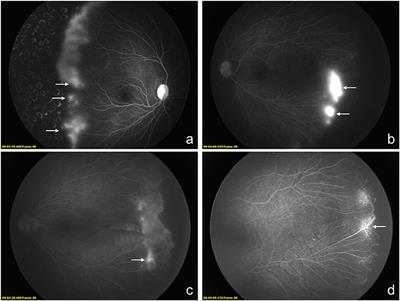

Published on 24 Jan 2022

in Ophthalmology